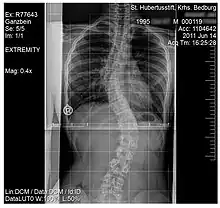

Scoliosis

.jpg.webp)

Scoliosis, is a medical condition where a person's spine has several irregular curves that are located between the neck and the pelvis.[8] Symptoms of scoliosis in mild cases usually exhibit abnormal posture, back pain, tingling or numbness in the legs and in worse cases can exhibit breathing problems, fatigue, permanent deformities and in rare cases heart problems.[8]